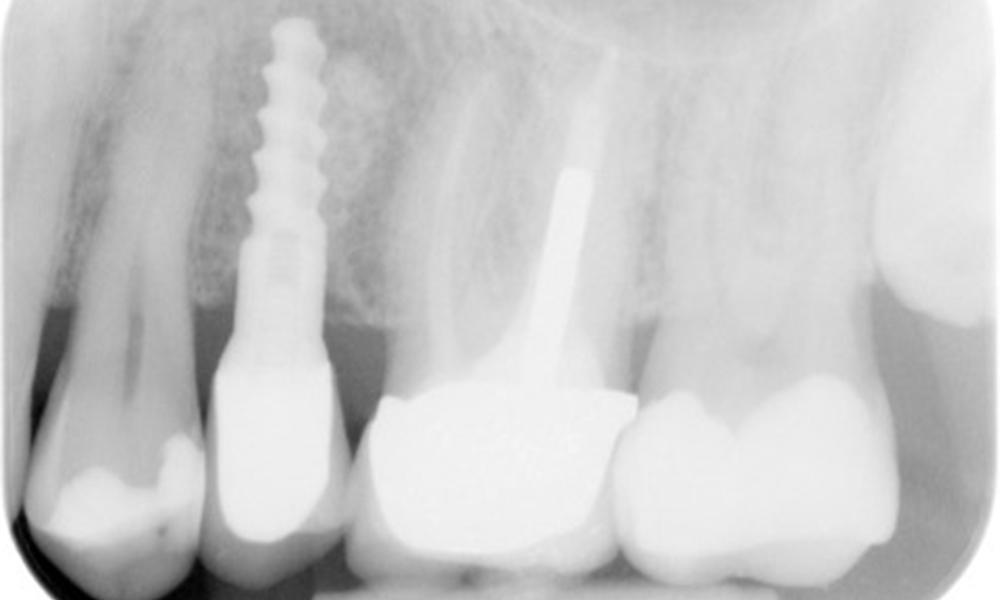

OPG: 29/02/2024

The X-ray image shows the bone loss

The X-ray images show the bone loss.